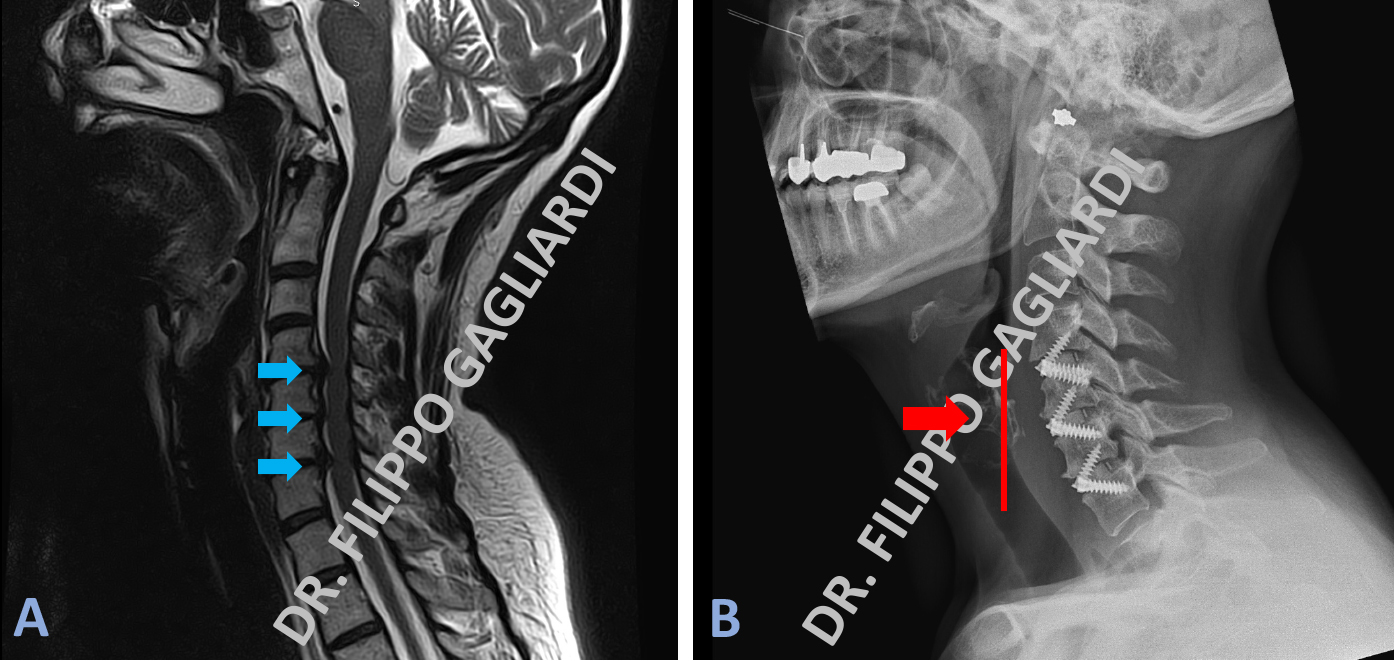

Caso di triplice ernia discale cervicale (Figura A) trattata con l’asportazione del disco intervertebrale malato corrispondente ed il posizionamento di 3 gabbiette in titanio munite di piccole viti che le fissano ai corpi vertebrali dando la massima stabilità all’impianto e senza avere necessità di mettere placche di titanio davanti alle vertebre per bloccare le gabbiette. Il controllo post-operatorio (Figura B) mostra il corretto posizionamento del sistema con il ripristino della fisiologica lordosi cervicale.

Caso di frattura della quinta vertebra cervicale con scoppio del corpo vertebrale a causa di un incidente della strada. Le frecce azzurre nelle Figure A e C dimostrano lo RX e la TC del collo. Evidente la frattura e la lussazione vertebrale.

Per ricostituire la stabilità vertebrale il Paziente è stato sottoposto ad un intervento in due tempi. La prima fase passando da davanti (tempo anteriore) e poi dietro (tempo posteriore). L'intervento è consistito in una corpectomia (asportazione del corpo vertebrale) della vertebra fratturata. Si è passati, poi, al posizionamento di una protesi espandibile (cage + placca) per via anteriore e viti di stabilizzazione posizionate per via posteriore (frecce rosse Figura B, D, E).

Corpectomia vertebrale cervicale.